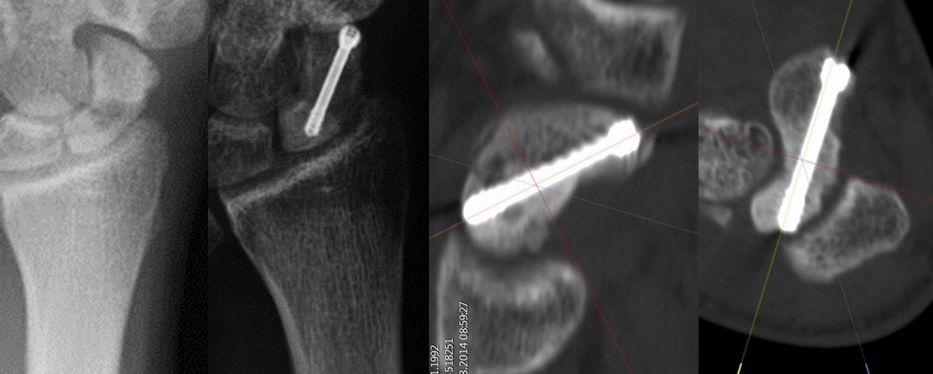

Behandlung eines fehlverheilten Kahnbeinbruches durch Knochentransplantation und Spezialschraube